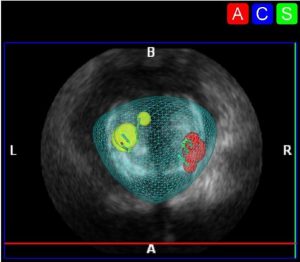

La Biopsia Prostatica in Fusione di Immagini permette di sovrapporre le immagini delle aree della prostata sospette per tumore identificate alla Risonanza Magnetica Multiparametrica con quelle dell’Ecografia al momento della biopsia cosí da mirare e colpire direttamente le zone di rilievo evitando biopsie inutili e di mancare il target.